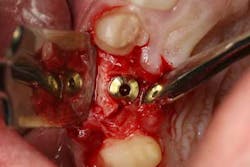

Using the surgical index as a reference, a 3.8 x 12 tapered implant was placed in a prosthetically driven manner. During placement, a 3 x 3 mm fenestration of the buccal plate occurred at the apical extent of the implant. Using a combination of enamel matrix derivate mixed with cortico-cancellous allograft placed in a bone syringe, the area of fenestration was grafted. Although the implant achieved 35 Ncm of stability, a cover screw was placed and primary coverage was achieved. A conventional two-stage procedure was selected because of the regenerative demands of this particular case. The area was then temporized with a newly fabricated lab-generated acrylic bridge with careful attention to pontic site development.